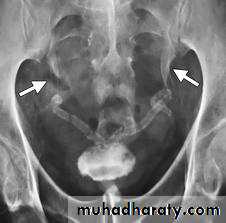

-Over 90% of calculi are radiopaque on plain films and virtually all on CT as very sensitive for detection of calculi, even those that appear radiolucent on plain film.

-Plain film may be useful in demonstrating calculi.

• Ddgx of stone on KUB :

• 1. Gall stone

• 2. calfied LN , cartilage ,fibroid,

• 3. Phlebolith: round, lucent centre.